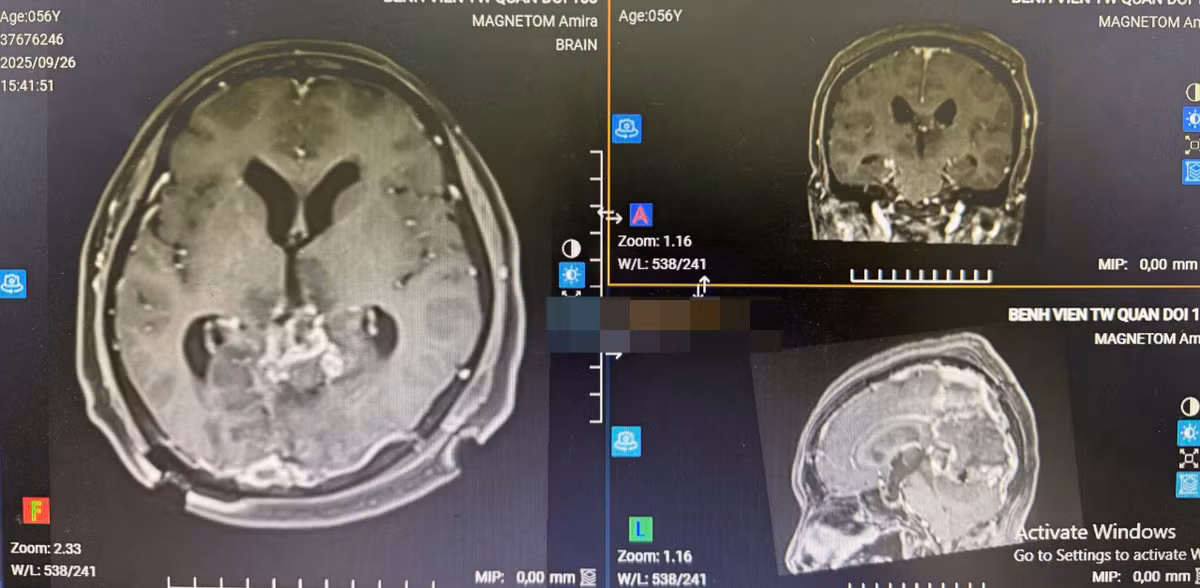

Sau phẫu thuật 2 ngày, bệnh nhân tỉnh táo, không liệt tay chân, được chuyển về khoa chăm sóc hậu phẫu. Chụp kiểm tra sau mổ, khối U đã được lấy hết, bệnh nhân được ra viện.

Tuy nhiên, niềm vui của gia đình, bệnh nhân và kíp phẫu thuật vẫn không được trọn vẹn vì thị lực của bệnh nhân không phục hồi. Hy vọng trong thời gian tới, nhờ sự chăm sóc của gia đình và điều trị của các bác sĩ, tình trạng bệnh nhân có thể tốt lên để có thể tự chăm sóc bản thân.

Phim chụp CT sau mổ - Ảnh BVCC